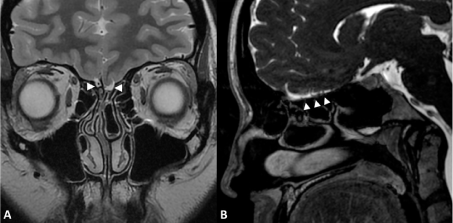

Figure 1: Normal olfactory bulbs.

MRI of normal-size olfactory bulbs (arrowheads) on coronal T2-weighted imaging (A) and sagittal Fast Imaging Employing Steady-state Acquisition, FIESTA (B). Olfactory sulci are well seen (star). View Figure 1